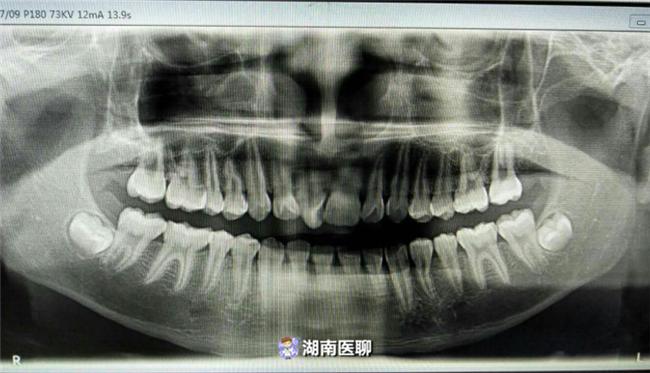

和医生交换意见,先是检查牙齿健康问题,接着就是拍片,拍片子是为了看你牙齿和骨骼的发展方向,根据拍片情况制定准确的矫治方案。

拔牙是为了腾空间,给那些因牙齿拥挤导致不整齐的牙齿归位。上图展示的是未拔牙病例。